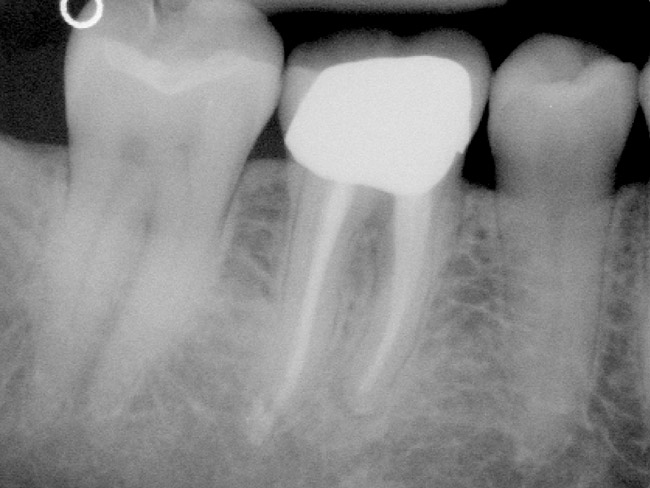

Figure 4a  Tooth No. 30 Nonsurgical root canal treatment had been completed 5 years before. The periapical radiograph revealed periradicular radiolucencies (periapical and in the furcation area).

Figure 4a

Figure 4b  The patient was asymptomatic, and periodontal probing depths were within normal limits; however, a new crown restoration was planned. Nonsurgical endodontic re-treatment was initiated. The intracoronal picture shows the previously treated 4 canals with infected gutta-percha filling.

Figure 4b

Figure 4c  Under high magnification, a furcation canal (Figure 4C) and a third distal canal (Figure 4D) were located.

Figure 4c

Figure 4d  Under high magnification, a furcation canal (Figure 4C) and a third distal canal (Figure 4D) were located.

Figure 4d

Figure 4e  The postoperative radiograph shows the re-treated tooth with 5 main canals.

Figure 4e

Figure 4f  The 1-year recall radiograph demonstrates the complete resolution of the periradicular radiolucencies.

Figure 4f